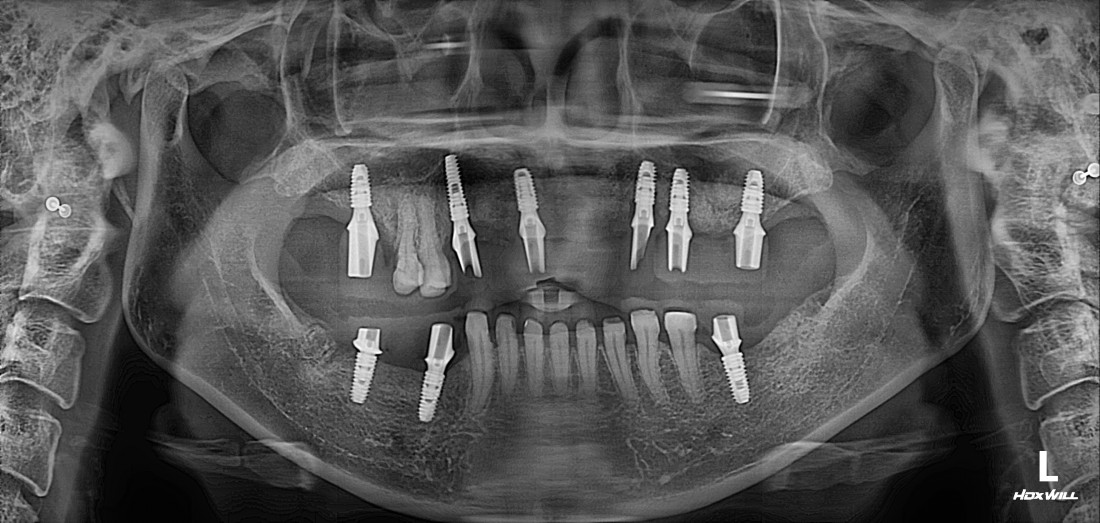

광주 상악임플란트 치과는

전체 임플란트 수술도

단 2번의 수술만으로

완성합니다.

광주 상악임플란트 치과에서는

위 / 아래 전체 임플란트를

붓기, 출혈, 통증을 최소화할 수 있는

디지털 가이드 임플란트 수술방법으로

단 2번의 수술만으로 완성하고 있습니다.